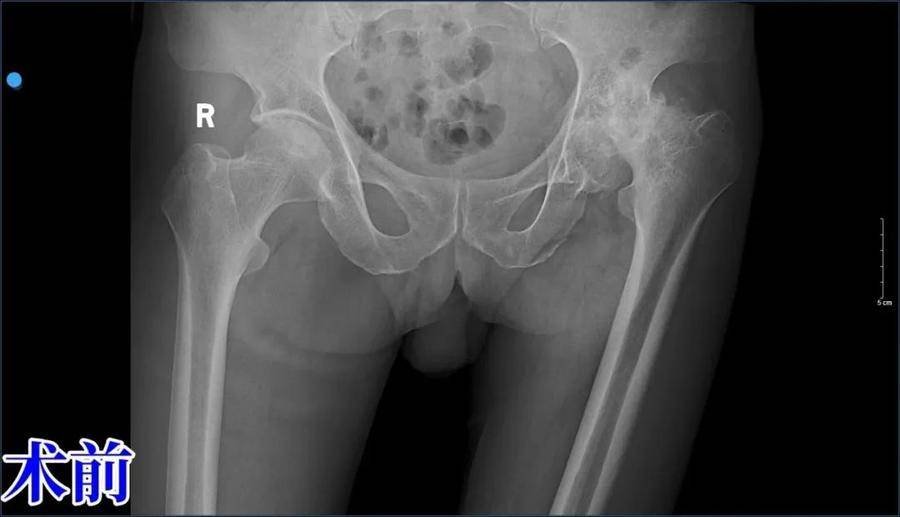

不久前,一位左髋关节疼痛长达15年的患者,因左下肢活动障碍、无法伸直,以及肺功能严重损害(矽肺)的困扰,来到了济南南郊医院寻求治疗。面对如此复杂的病情,骨一科的孙焕科主任没有丝毫退缩,他深知,每一次手术都是对生命的敬畏和对医术的考验。